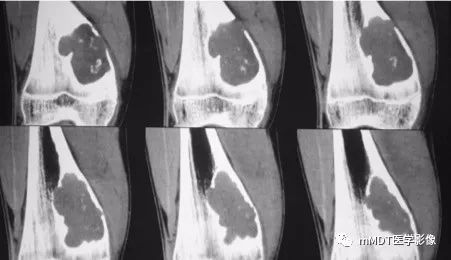

病史:15岁男性,右膝不适2年,行走及上楼时疼痛不明显。查体:右膝内侧膨隆,屈曲略受限,局部皮温正常,皮肤完整。影像资料如下:

CT冠状面骨窗

CT见病变位于股骨远端干骺端,呈分叶状、偏心膨胀性生长,密度欠均匀,整体低于肌肉密度,部分区域密度接近水,其内可见点状、线状、弧形、圆形的高密度影,大部分边缘硬化,局部深侵蚀骨内膜,局部骨壳不完整。MR上,T1WI信号略低于肌肉,T2压脂呈现不均匀高信号,未见明确软骨小叶结构及纤维分隔,周围可见水肿。